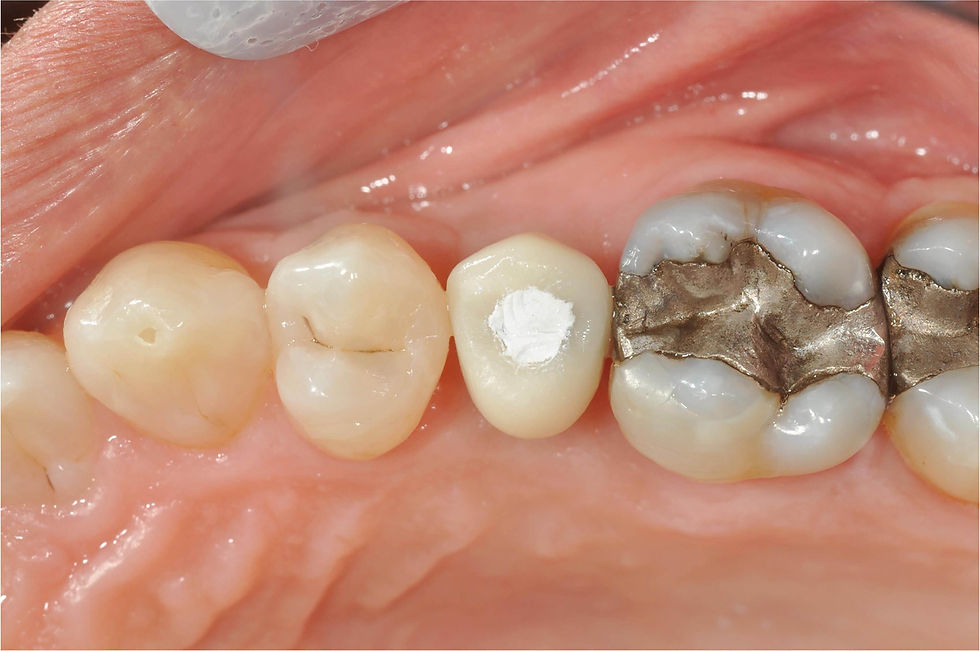

Healing at 3 months.

Positioning of the final post: soft tissues are thickened and already partially adapted.